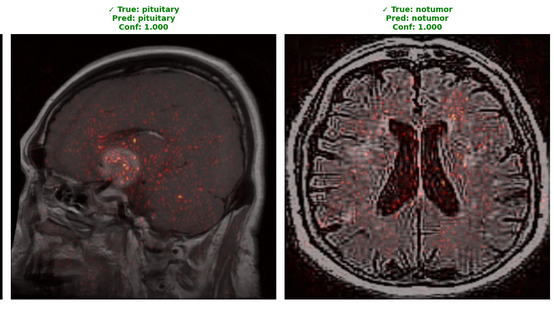

The Inception-ResNet-v2 Grad-CAM visualizations in figure 13 show greater explainability with the left sagittal view of a pituitary tumor showing concentrated red activation localized to the sella turcica region where pituitary tumors typically occur, and the right axial view of the normal brain showing diffuse bilateral patterns of activation. Additionally, both predictions have complete confidence (1.000); for the pituitary case, it appropriately focuses attention on the midline tumor location, and the notumor case appropriately distributes attention to cortical regions without focal abnormalities. By integrating the ability to visualize different anatomical planes (sagittal and axial), as radiologists would typically examine multiple MRI views, our study drastically improves clinical interpretability as our heatmaps overlap perfectly with clinically relevant locations of a pituitary tumor and notumor, confirming the pretrained model learned sets of features can be used for medical diagnoses.

Refer to caption

Figure 13: Grad-CAM visualization of Inception-ResnNet V2 predictions.